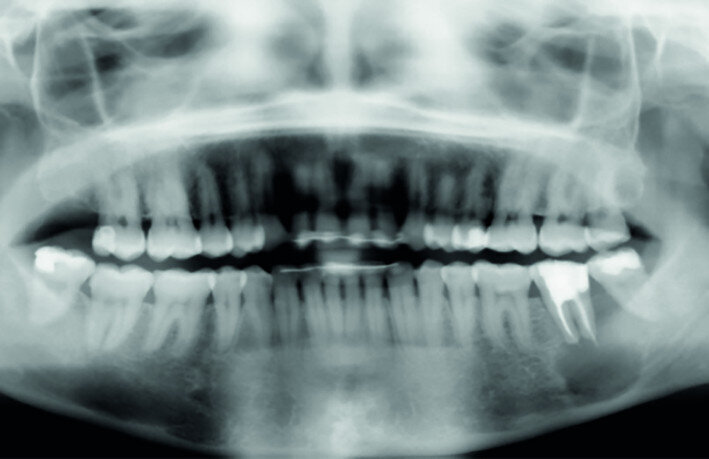

Fig. 15a: Radiograph: Pre-op panoramic.

The left mandibular second molar of a 35-year-old female patient had been compromised because of a vertical root fracture and a large periapical lesion was present. After explanation and informed consent, the treatment was scheduled. The right mandibular third molar was preferred as a donor to the left mandibular third molar because of a more compatible anatomy and for an easier stabilisation. After local anaesthesia of both the donor and the recipient sites with 2 per cent mepivacaine with 1:100,000 adrenaline, the left mandibular second molar was extracted and the alveolus debrided. Then the donor tooth was atraumatically extracted, quickly repositioned in the recipient site and stabilised with sutures at about 1.5–2.0 mm of infraocclusion. An antibiotic (amoxicillin/clavulanic acid, 1 g, by mouth twice a day for five days) and a non-steroidal anti-inflammatory drug (ibuprofen, 600 mg, by mouth twice a day for five days) were prescribed, along with rinses with 0.2 per cent chlorhexidine. The sutures were removed after two weeks and endodontic treatment was performed after three months. The periapical lesion healed and the tooth was fully functional after 12 years (Figs. 14a–d & 15a–d).